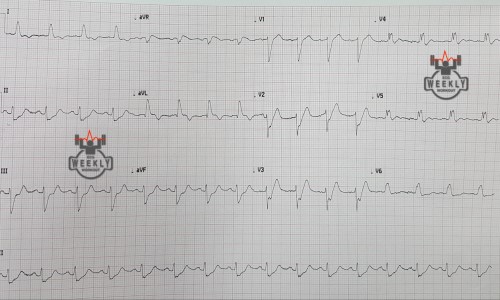

There is 1mm concordant ST elevation in aVL (= 5 points)

There is concordant ST depression in V2-5 (= Sgarbossa positive).

There is 1mm concordant ST elevation in II, III, aVF (= 5 points)

There is 1mm concordant ST elevation in aVL, V4-6 (= 5 points)

There is 1mm concordant ST elevation in aVL (= 5 points)

There is concordant ST depression in V1-3 (= Sgarbossa positive).

There is 1mm concordant ST elevation in aVL, V5-V6 (= 5 points)

There is 1mm concordant ST elevation in I, aVL, V5 (= 5 points)

There is concordant ST depression in V1-3 (= Sgarbossa positive).

There is concordant ST depression in V3 (= Sgarbossa positive).

There is concordant ST depression in V3 (= Sgarbossa positive).

There is 1mm concordant ST elevation in I, aVL (= 5 points)

There is concordant ST depression in V3 (= Sgarbossa positive).

≥ 25% of the depth of the preceding S-wave : Revised Sgarbossa criteria

≥ 25% of the depth of the preceding S-wave : : Revised Sgarbossa criteria